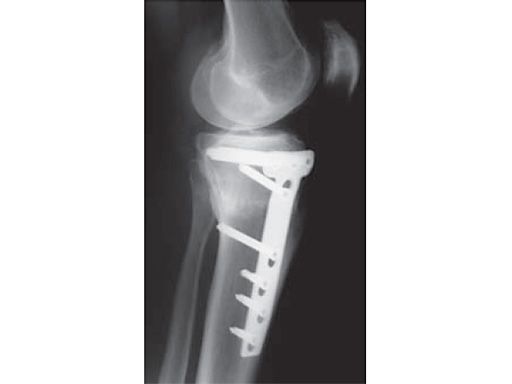

The correction is planned on a long-leg standing x-ray. After surgery, the mechanical axis should pass through a point 63% on the lateral side of the total width of the tibial plateau in the frontal plane. A transverse or slightly oblique incision is used to avoid damage to the saphenous nerve. The distal fibers of the medial collateral ligament are detached from the tibia. Under fluoroscopic control, two wires are placed in the proximal tibia marking the transverse osteotomy plane. The cut usually starts at the upper margin of the pes anserinus and ends at the tip of the fibula on the lateral side. The wires are placed exactly parallel to the tibial plateau thus taking into consideration the individual tibial slope of the patient. An incomplete cut of the posterior two-thirds of the proximal tibia is performed with an oscillating saw guided by the wires. Continuous irrigation avoids burn injury to the bone. A second osteotomy is now performed in the anterior third of the tibia in an angle of 100 ending above the patellar tendon insertion. A smaller saw blade is used and the complete anterior cortex is cut exactly in the frontal plane. The osteotomy is now gradually opened by inserting flat chisels or a spreader-chisel into the posterior osteotomy cleft. This process may take some minutes and can usually be completed without fracture of the lateral cortex. A bone spreader is now placed in the posteromedial edge of the tibia and the chisels are removed. The leg is extended and the correction is checked with the fluoroscope. A long metal rod is placed between center of the hip joint and center of the ankle joint. The projection of this rod should be at the planned point of correction on the tibial plateau lateral of the midline. Eccentric collapse of the medial joint space may cause accidental overcorrection. In this case pressure on the foot may simulate loading and body weight. The correction can be fine-tuned by opening or closing the spreader. The TomoFix Medial Tibia Plate is now placed in a subcutaneous pocket. The implant is precontoured and usually fits well to the bone surface. The distance holders avoid compression of the medial collateral ligament and the pes anserinus. Three proximal bolts are placed near the subchondral sclerosis zone. The position of the bolts is adapted to the anatomy of the proximal tibia giving optimum purchase for the bolts. An oblique lag screw is inserted distal to the osteotomy. This screw in the first combination hole allows careful compression of the lateral osteotomy hinge and pretensioning of the implant. A stab incision is created on the shaft and the implant is fixed monocortically with bolts. The lag screw and the distance holders are replaced by bolts. The medial collateral ligament is released longitudinally to reduce medial compartment pressure and the wound is closed in layers. An overflow drain may be used. Clinical and experimental work has proven that when this technique is closely followed, corrections up to and over 15 mm can be performed without bone grafting or use of bone substitutes.

The patient is mobilized on crutches on day one after surgery. Partial weight bearing is allowed from the beginning. Biomechanical and RSA studies have proven that postoperative loading of the implant by body weight in standard partial weight bearing and early full weightbearing conditions did not cause loss of correction. Our group now allows the patients to walk without crutches as soon as the postoperative pain allows after this type of surgery. Members of the Knee Expert Group (KNEG) have presently implanted over 1,500 TomoFix medial tibia. The results are extremely positive in respect to osteotomy healing, implant failure, and surgical complications.